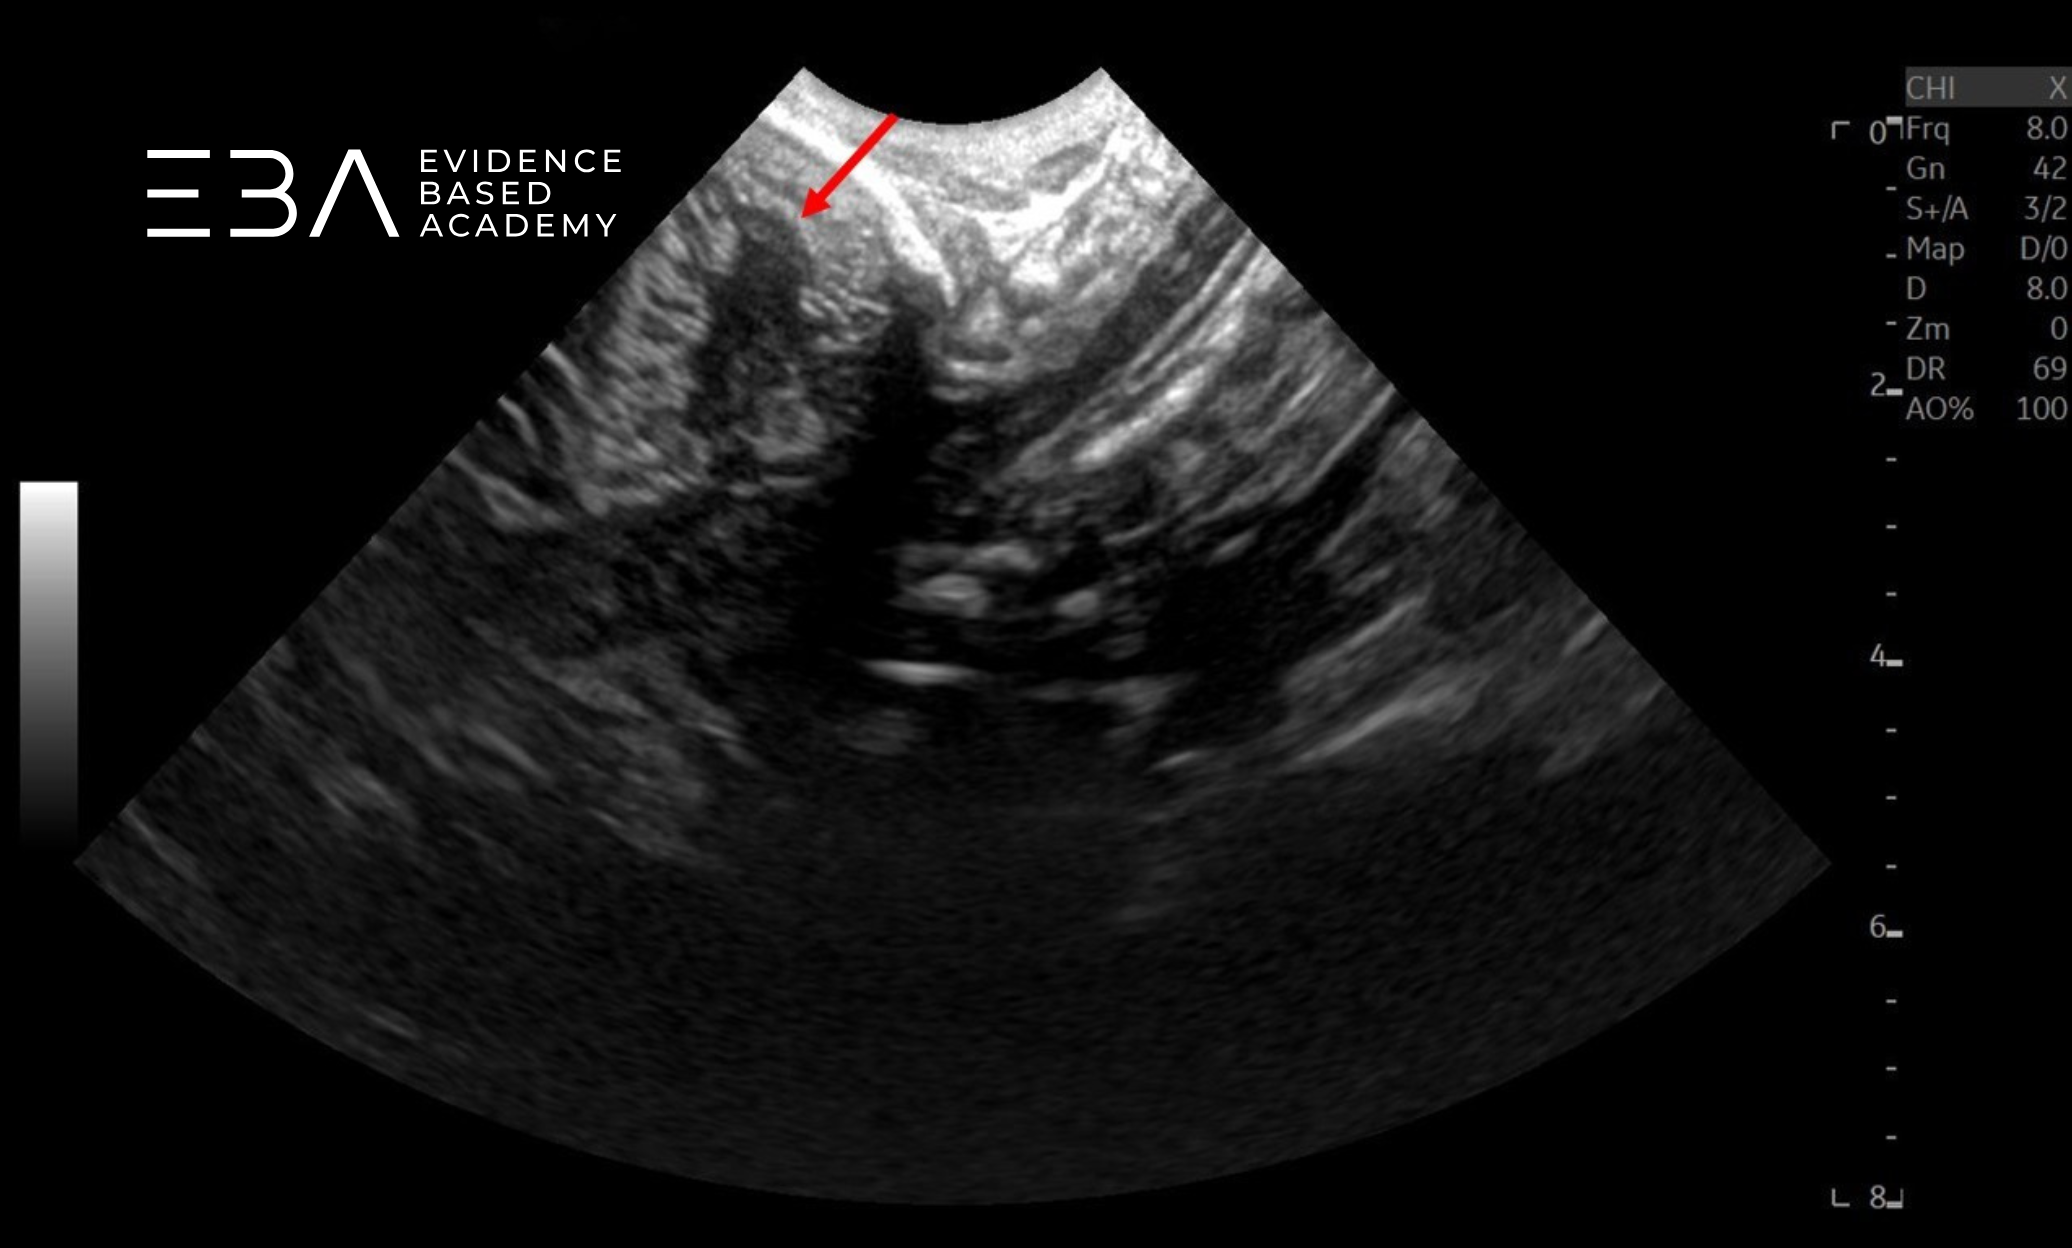

zdj. 15

Głowica sektorowa (projekcja strzałkowa). Strzałką zaznaczono robak móżdżku.